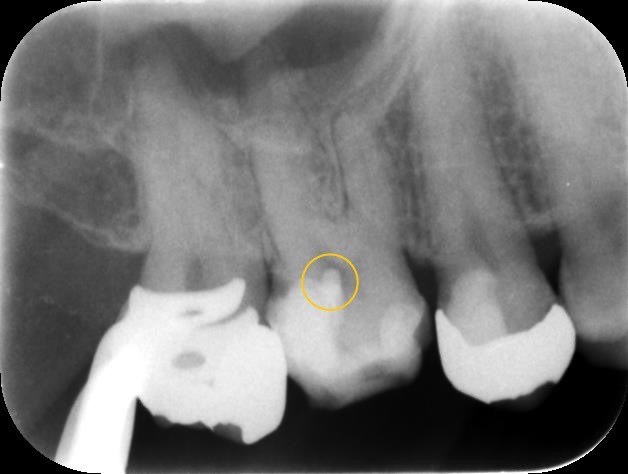

右上の6番目の歯を1年半前に虫歯治療して、銀歯が入ってる状態です。

レントゲンで診ると確かに神経の近くまで削ってることがわかります🔍

こちらが治療後のレントゲンです。